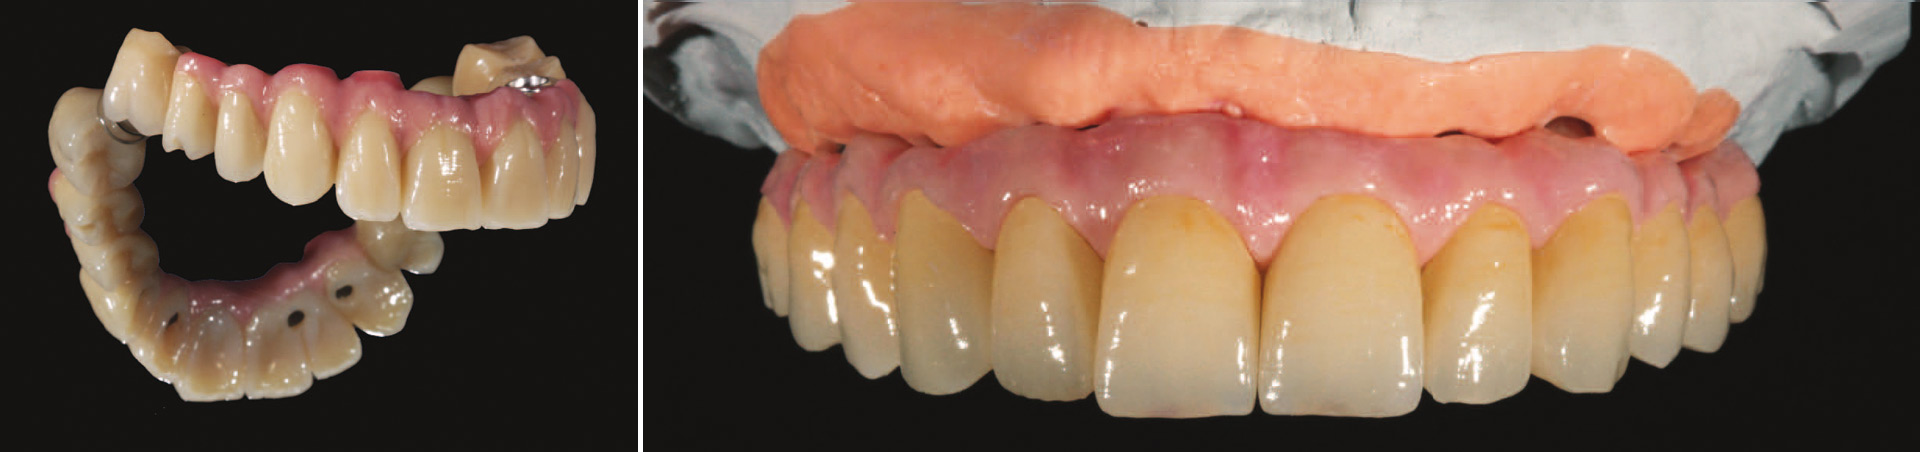

Die fest verschraubte Brücke

Wie schon bei der temporären Brücke, wird diese Versorgung fest auf den Implantaten verschraubt und kann nicht herausgenommen werden. Der Unterbau kann aus Metall oder aus einer speziellen Keramik erstellt werden. Die Zähne und das künstliche Zahnfleisch werden aus einer robusten und ästhetisch schönen Keramik gefertigt. So entstehen funktionelle, schöne und langlebige Zähne für ein strahlendes Wohlgefühl.